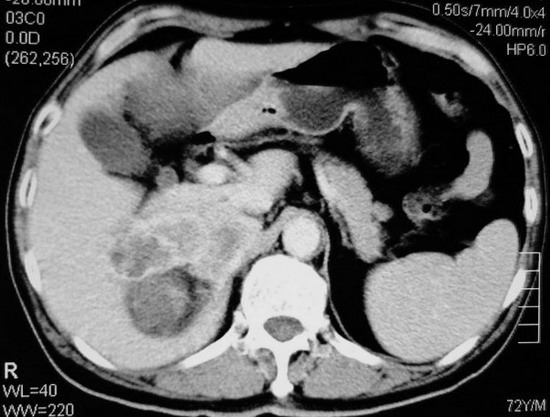

以下是引用杀毒软件在2008-11-17 19:15:00的发言:[br]考虑------右肾癌合并肾静脉---同侧肾上腺受侵可能性大

以下是引用zjzjr在2008-11-17 20:45:00的发言:[br]考虑------右肾癌合并肾静脉---同侧肾上腺受侵可能性大及腹膜后淋巴结转移.